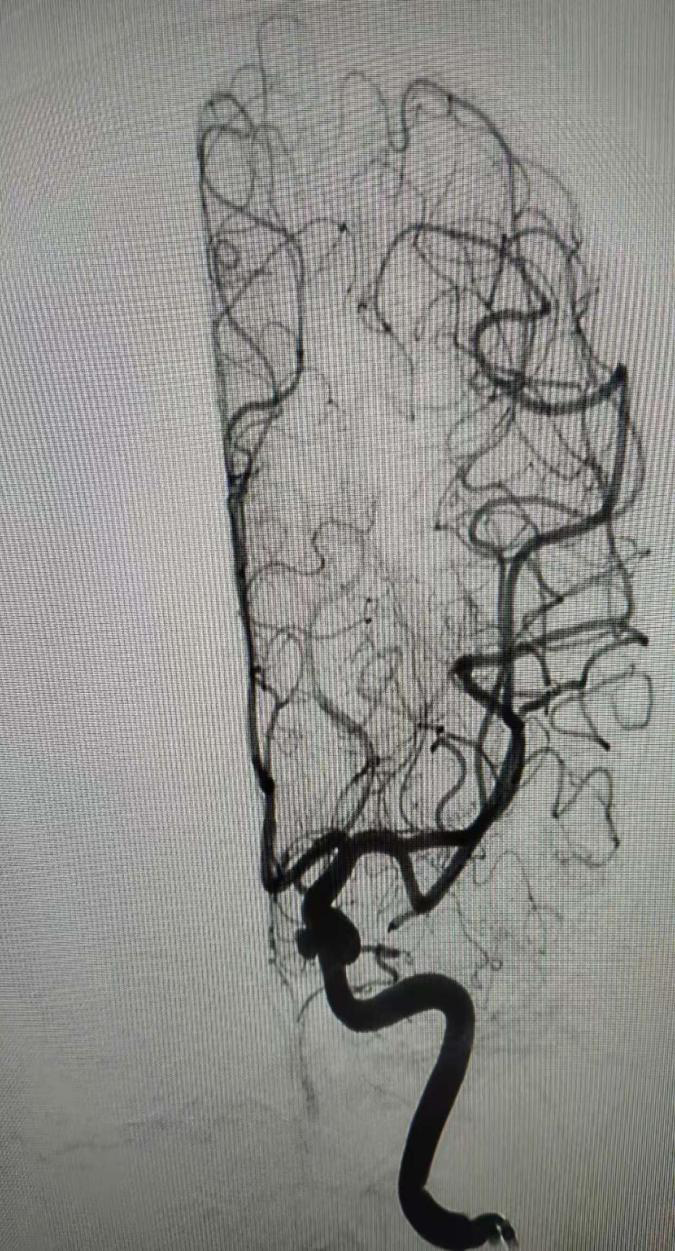

造影检查并做好手术预案: